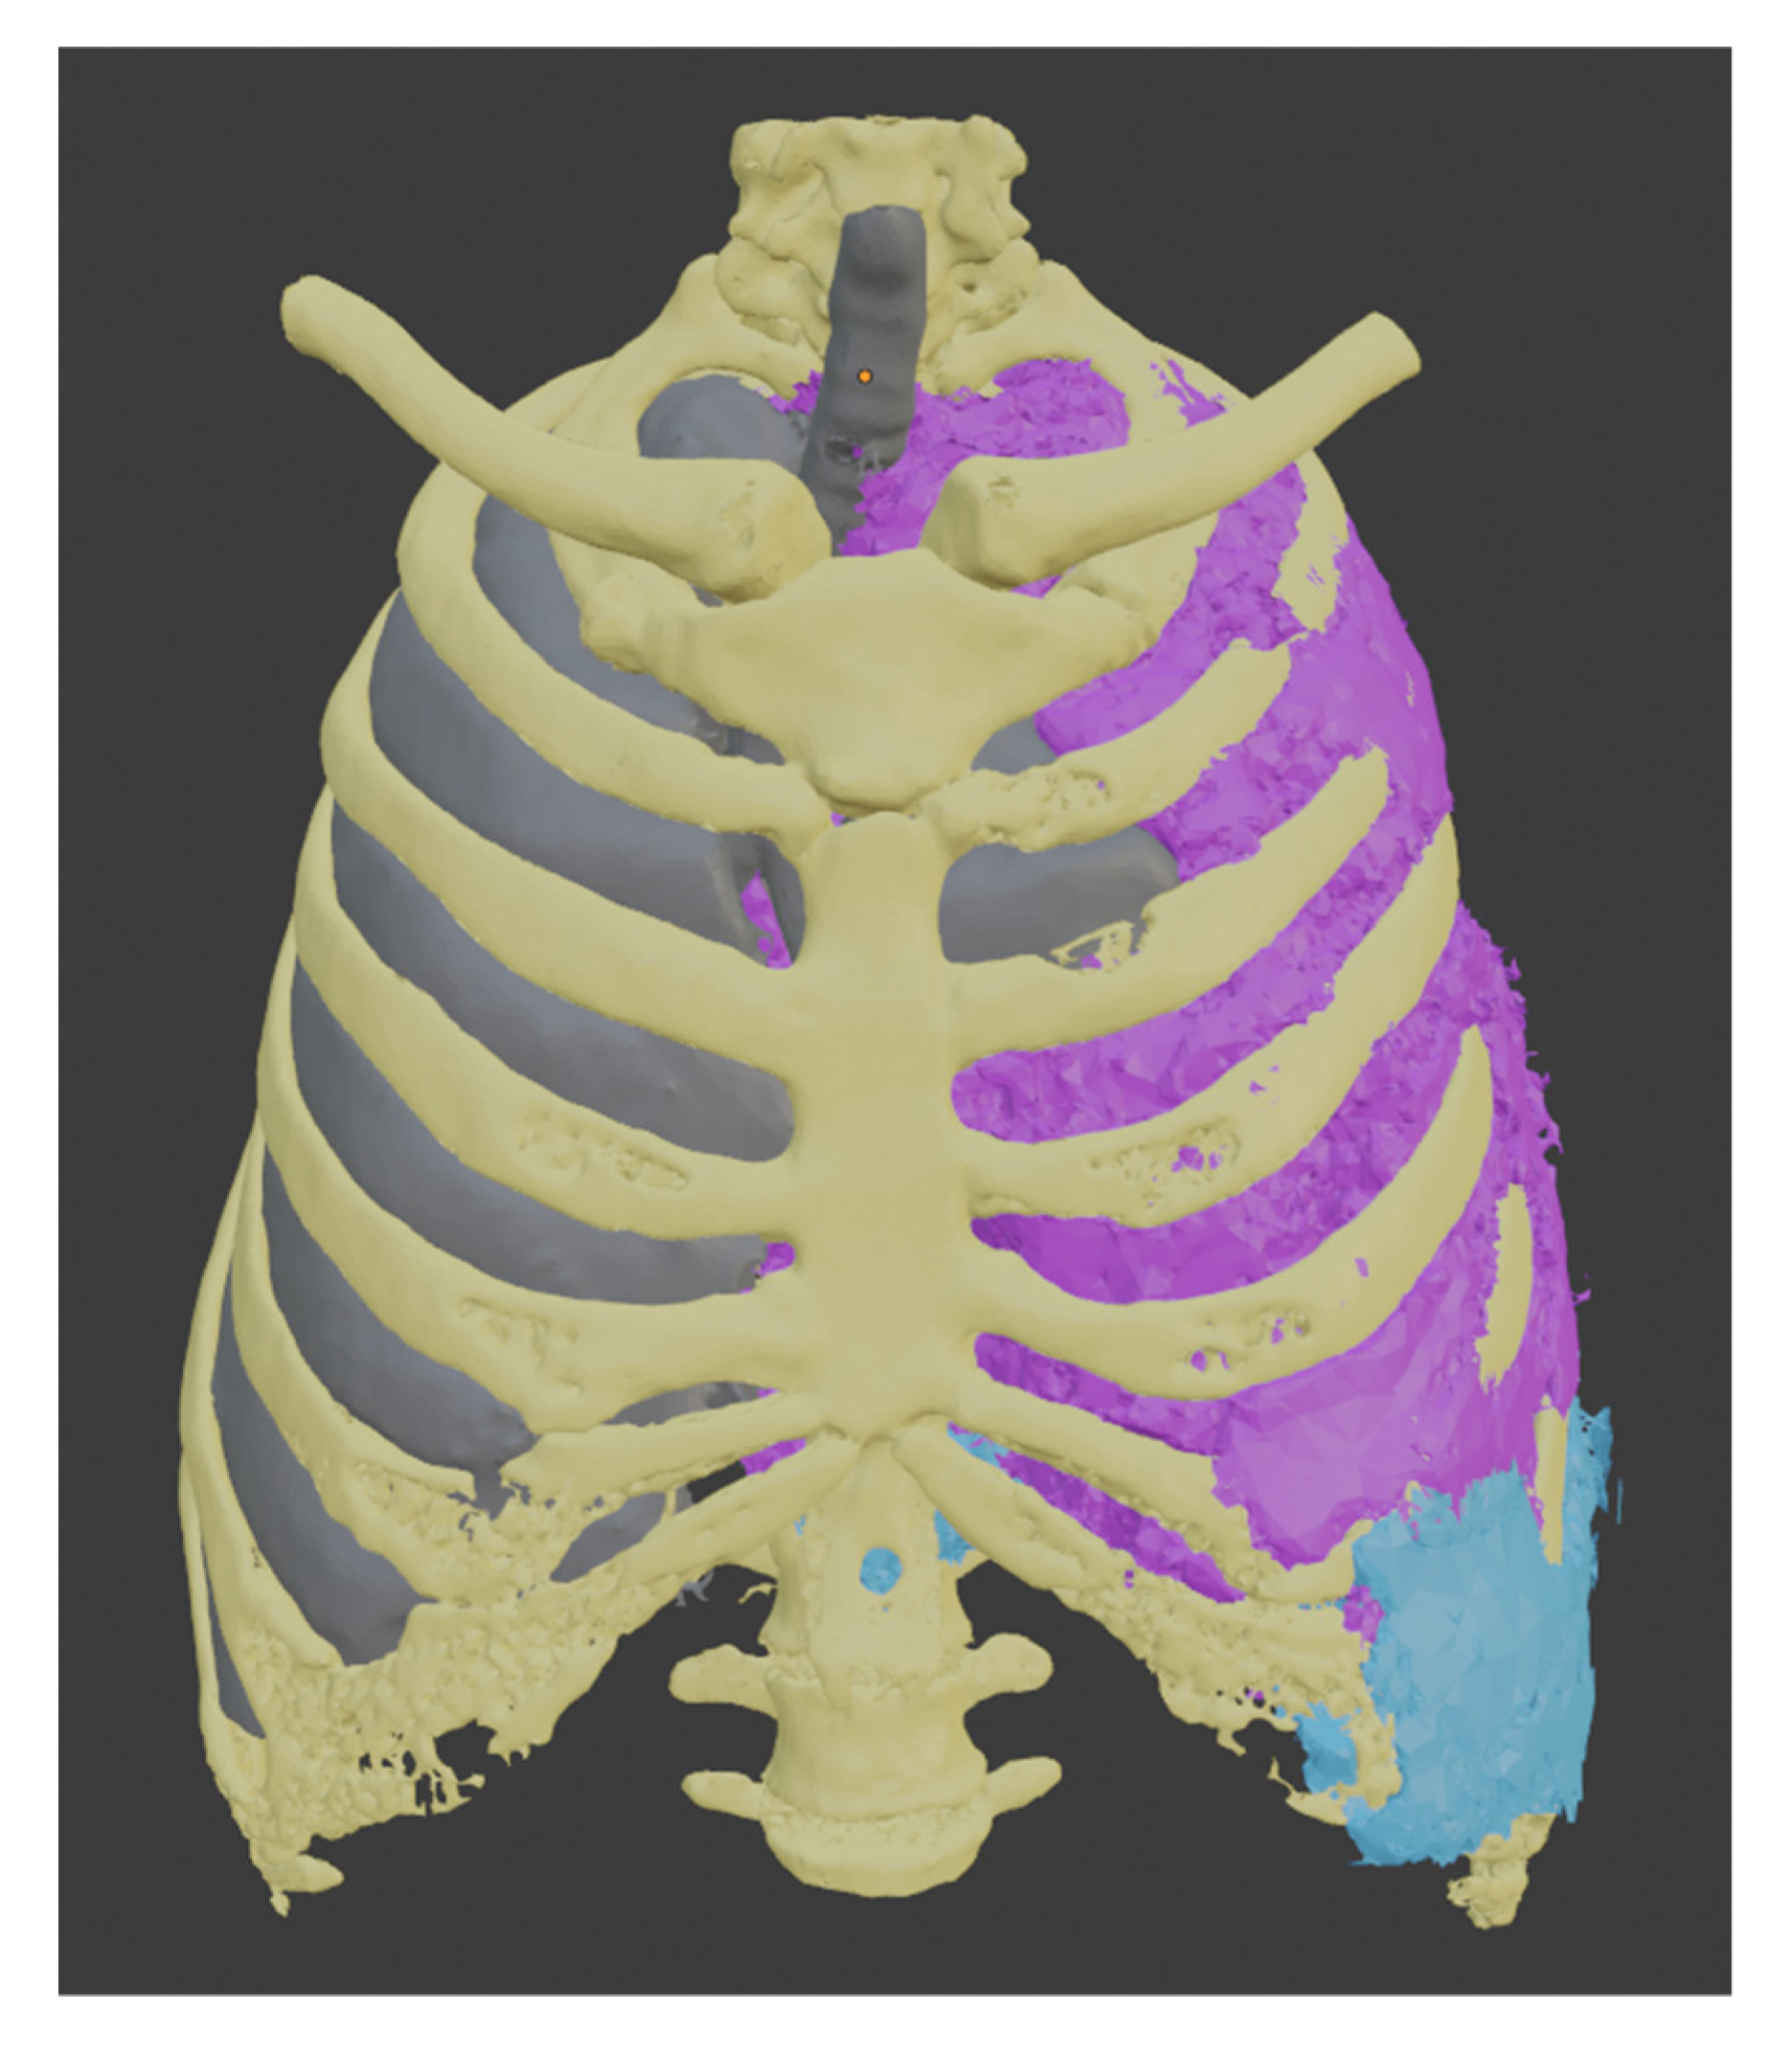

2.4. Tumor Segmentation Process

3. Results

Comparison of the Models Obtained from the Healthy Part of the Lung